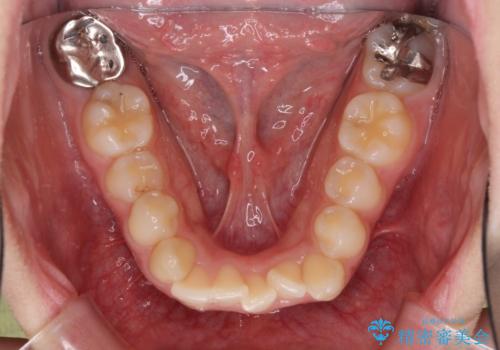

また、下顎骨の右側変位による右側臼歯の咬合を改善させるよう試みることとしました。

右側の咬合改善を目標に様々な手法を用いましたが、骨格的なズレによる不正咬合はインビザラインでは改善することができませんでした。